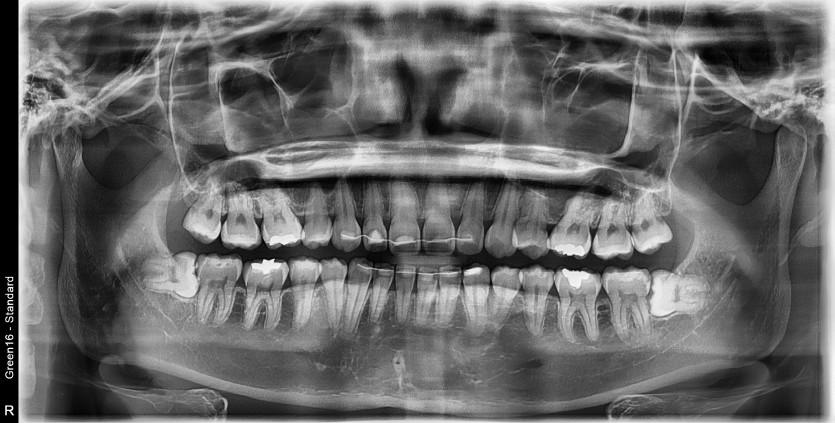

#38,48 사랑니 발치

구강 외과 전문의가 당일 발치했습니다.